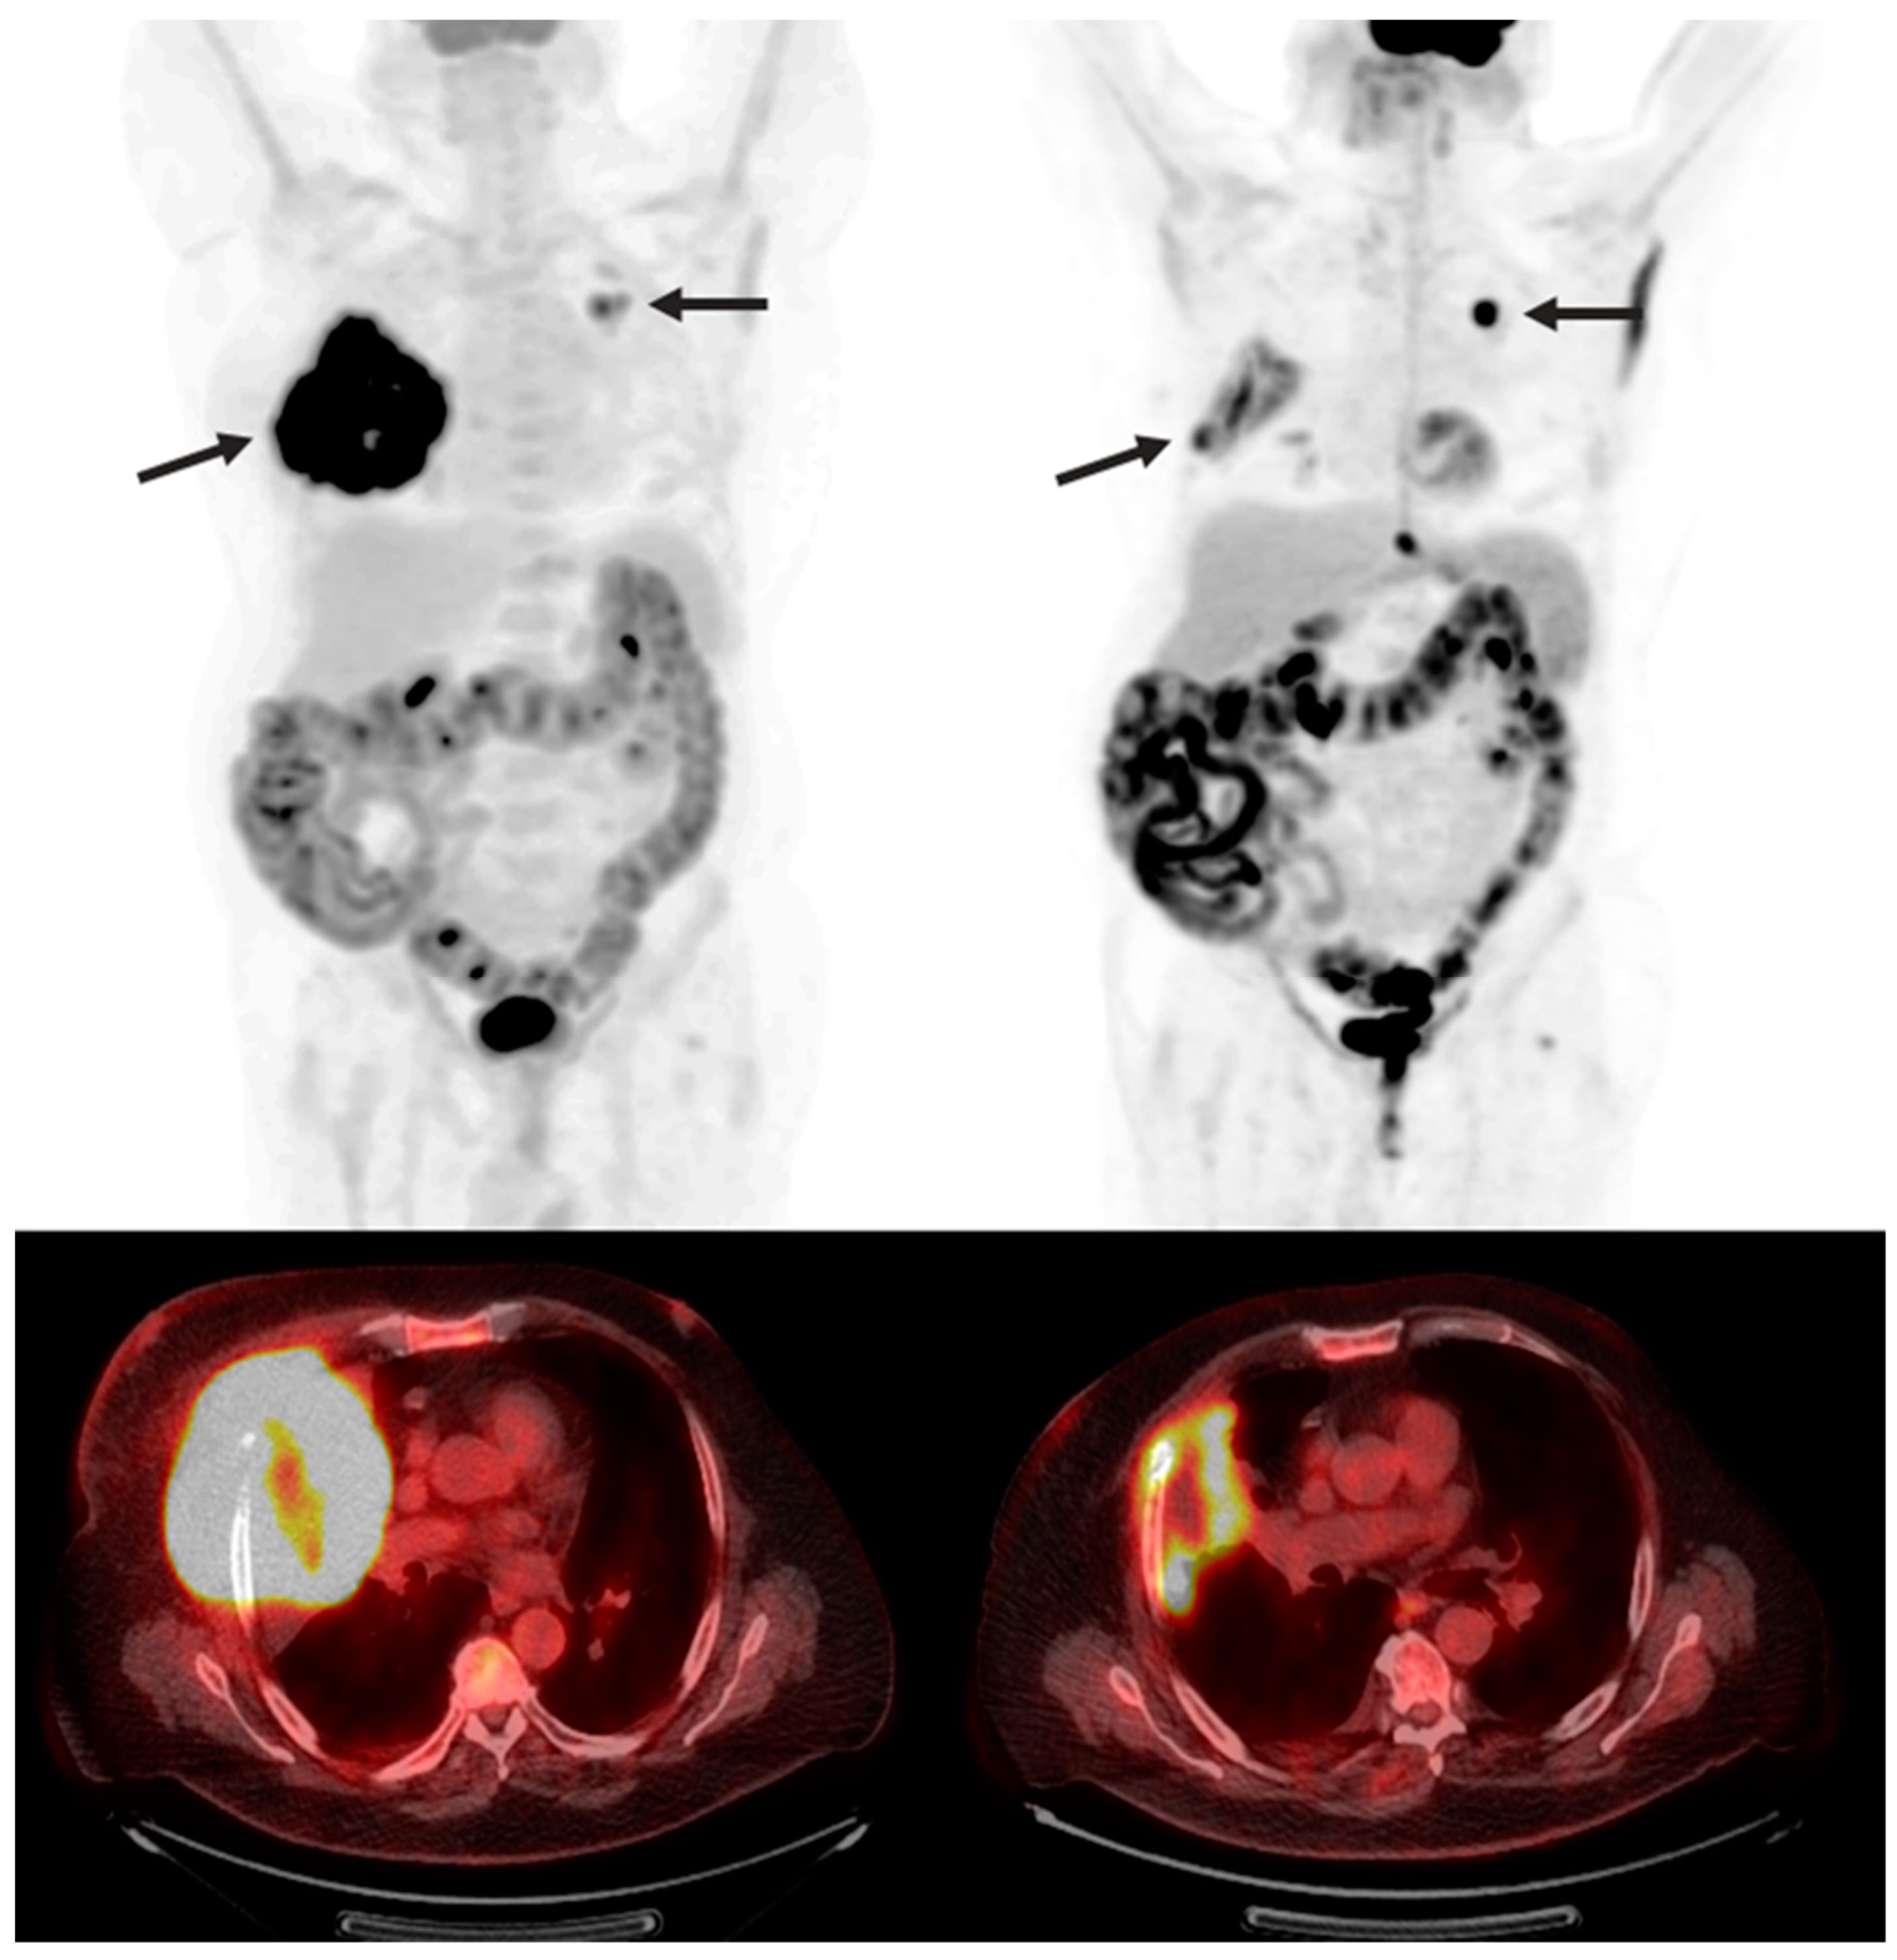

Figure 4.

A 70-year-old man with refractory diffuse large B-cell lymphoma. Maximum intensity projection and axial fused FDG PET/CT pre- (right) and 3 months post- (left) CAR T-cell therapy showing marked decrease in size and FDG uptake of right upper lobe lymphomatous mass invading the right chest wall (arrow). Slight increase in FDG uptake of left upper lobe pulmonary nodule (arrow), also suspicious for lymphoma.